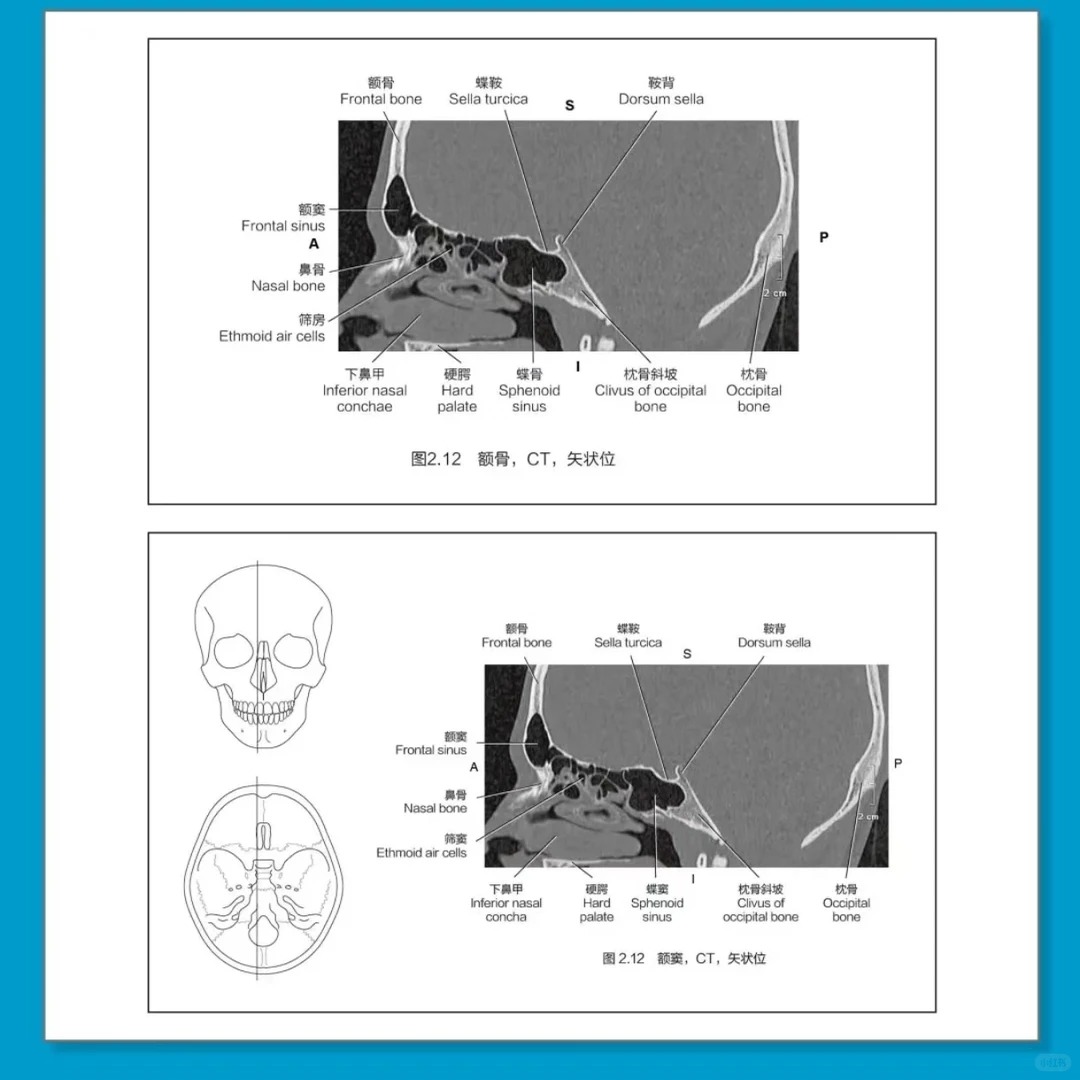

1. 高清影像全覆盖,细节拉满:1000+张高清影像图,涵盖全身所有关键断面,包括脑颅、面颅、脑、脊柱脊髓、颈、胸、腹、盆部及四肢,CT、MRI、3D图像、血管图像一应俱全,细节清晰、无模糊,精准呈现解剖结构的位置与形态,助力精准阅片[1][3]。

2. 手绘对照,直观易懂:搭配350+张手绘解剖示意图,与高清实图精准对应、对比呈现,将抽象的断层解剖结构具象化,清晰标注各部位名称,帮助快速区分解剖结构,破解断层解剖难懂、阅片找不到对应结构的难题,新手也能快速上手[1][3]。

3. 中英对照,双重赋能:所有解剖名词全部采用中英对照标注,标注规范、清晰不费眼,既能夯实断层解剖基础,牢记解剖名词,又能同步提升专业英语水平,适配医学考研、学术交流等需求[1]。

• 全身断层篇:第2-10章重点讲解脑颅和面颅、脑、脊柱脊髓、颈部、胸部、腹部、盆部、上肢和下肢的断层解剖结构,每个部位均配套高清影像图、手绘示意图,详细描述解剖结构特征[1][3]。

• 图文对照篇:1000+张高清影像图与350+张手绘解剖示意图精准对应,直观呈现断层解剖结构,标注清晰,帮助快速理解、记忆,破解阅片难点[1][3]。